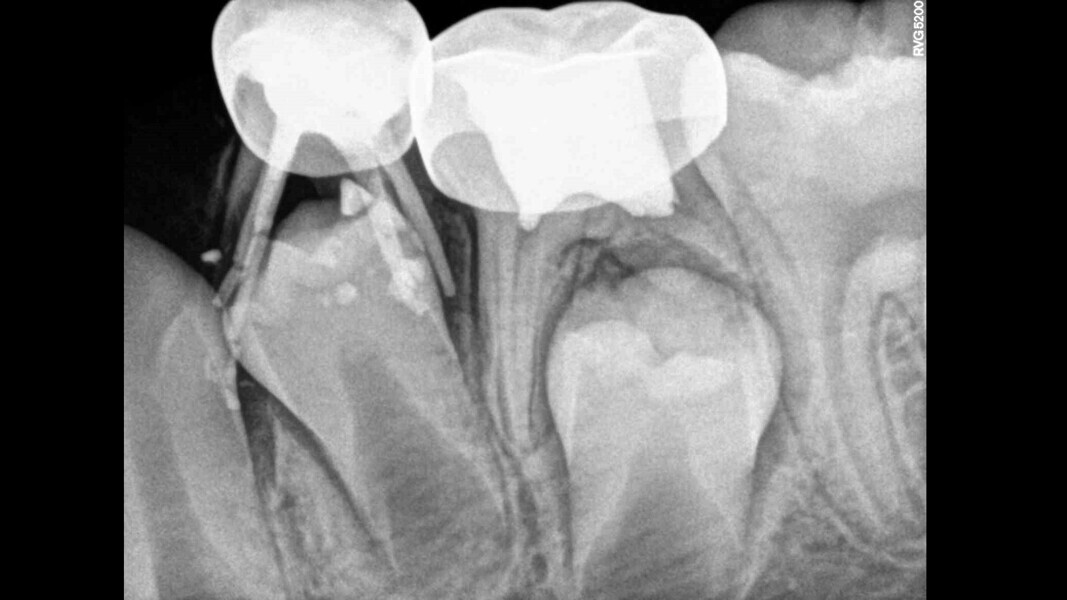

Case 2 (Figs. 5–9)

This male patient was 6 years and 7 months old and presented with severe tooth decay on the mandibular left first primary molar without any symptoms of pain. He experienced slight discomfort to percussion and palpation of the buccal gingiva. A buccal abscess and no mobility were observed. The radiograph showed a large area of interradicular bone loss. The tooth was diagnosed with pulp necrosis and an asymptomatic apical abscess. Pulpectomy was performed, and at a second appointment, a stainless-steel crown was placed upon confirming absence of signs or symptoms of disease. At the 14-month recall, no clinical pathology was detected and a normal eruptive process of the permanent premolars was observed in spite of the extrusion of the obturation material.